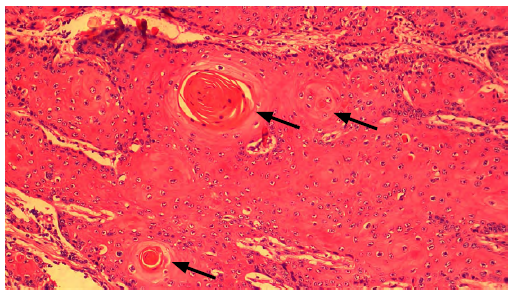

Los hallazgos microscópicos evidenciaron proliferación neoplásica maligna de origen epitelial con un patrón de crecimiento invasivo multilobular en glándula de meibomio y dermis superficial y profunda (figura 4) , islas o nódulos de diferentes tamaños, algunas formando estructuras quísticas que contienen abundante queratina laminar concéntrica-perlas de queratina (figura 5) , adicionalmente, núcleos redondos, ovalados, alargados e irregulares y úlcera focalmente extensa con múltiples áreas de necrosis (figura 6), fibrina severo infiltrado mixto linfoplasmocitario eosinofílico y supurativo difusa, dermatitis mixta ulcerativa y necrótica severa difusa con sobreinfección bacteriana y adenitis mixta severa difusa.

Masa tumoral. Estructuras en forma de nódulo formando perlas de queratina (flecha). Tinción H&E, 4x

FIGURA 5: Masa tumoral. Estructuras en forma de nódulo formando perlas de queratina (flecha). Tinción H&E, 4x

Fuente: elaboración propia.